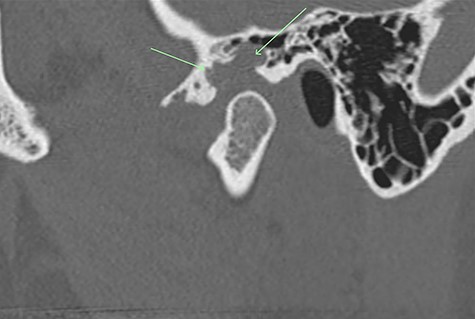

A 33-year-old woman complained of a 3-month history of left-sided TMJ morning stiffness. She had never been treated nor undergone any previous TMJ procedures and reported an unremarkable medical history. Examination findings showed a small left-sided preauricular swelling with tenderness worse at the joint level. Mouth opening restricted by pain was 35 mm. Normal excursive movements and no malocclusion or lateral deviation was observed. Computed tomography (CT) and magnetic resonance imaging (MRI) of the TMJs showed: superior joint space effusion, multiple small low-signal intensity foci within the fluid and extensive erosions within the glenoid fossa, articular eminence and root of the zygoma (Figs 1 and 2). This was reported to be highly suggestive of left-sided TMJ synovial chondromatosis.

Non-contrast CT TMJs. Sagittal view showing the left TMJ erosive lesion within the glenoid fossa and articular eminence (green arrow).